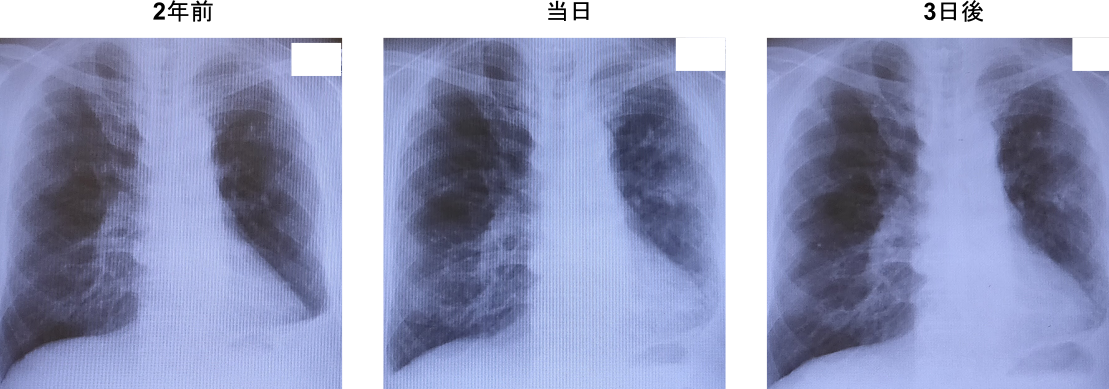

・胸部レントゲン

・胸部CT:左肺炎疑い、両側少量胸水

・当日:肺炎の診断。オーグメンチン250mg/アモキシシリン250mg x 朝夕/day開始

・3日後:Alb 3.4, Cr 1.9, CRP 6.015, WBC 8100, 好中球78.6%, リンパ球13.3%。喀痰排出困難あり、ホクナリンテープ2mg x 1枚/day開始